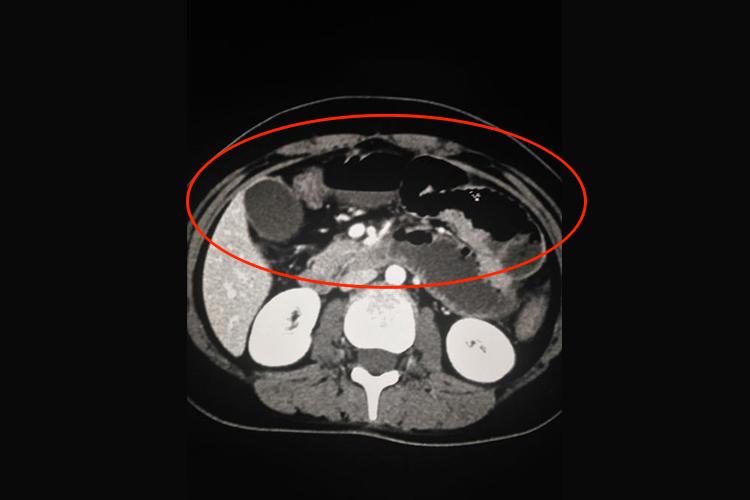

CT虽然不是诊断肠梗阻的主要方法,但有时有助于病因的诊断。肠梗阻时CT可显示扩张的肠曲,并可见多个肠腔内气-液平面、肠壁增厚以及直径增大。如果肠管互相融合成团,或与腹壁相连,提示为粘连性肠梗阻。如有肠套叠,则可显示出典型CT征象,出现三层肠壁征。患者还可出现腹痛、呕吐、腹胀等症状。